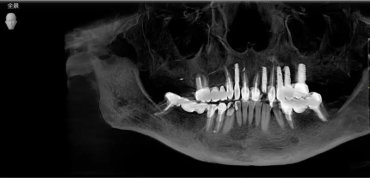

什么是健康的口腔 世界卫生组织关于口腔健康的五大标准:牙齿清洁,没有龋洞,没有疼痛感,牙龈颜色正常,没有出血的现象。 牙齿的常见病龋病:龋病发病广泛,表现为牙齿表面